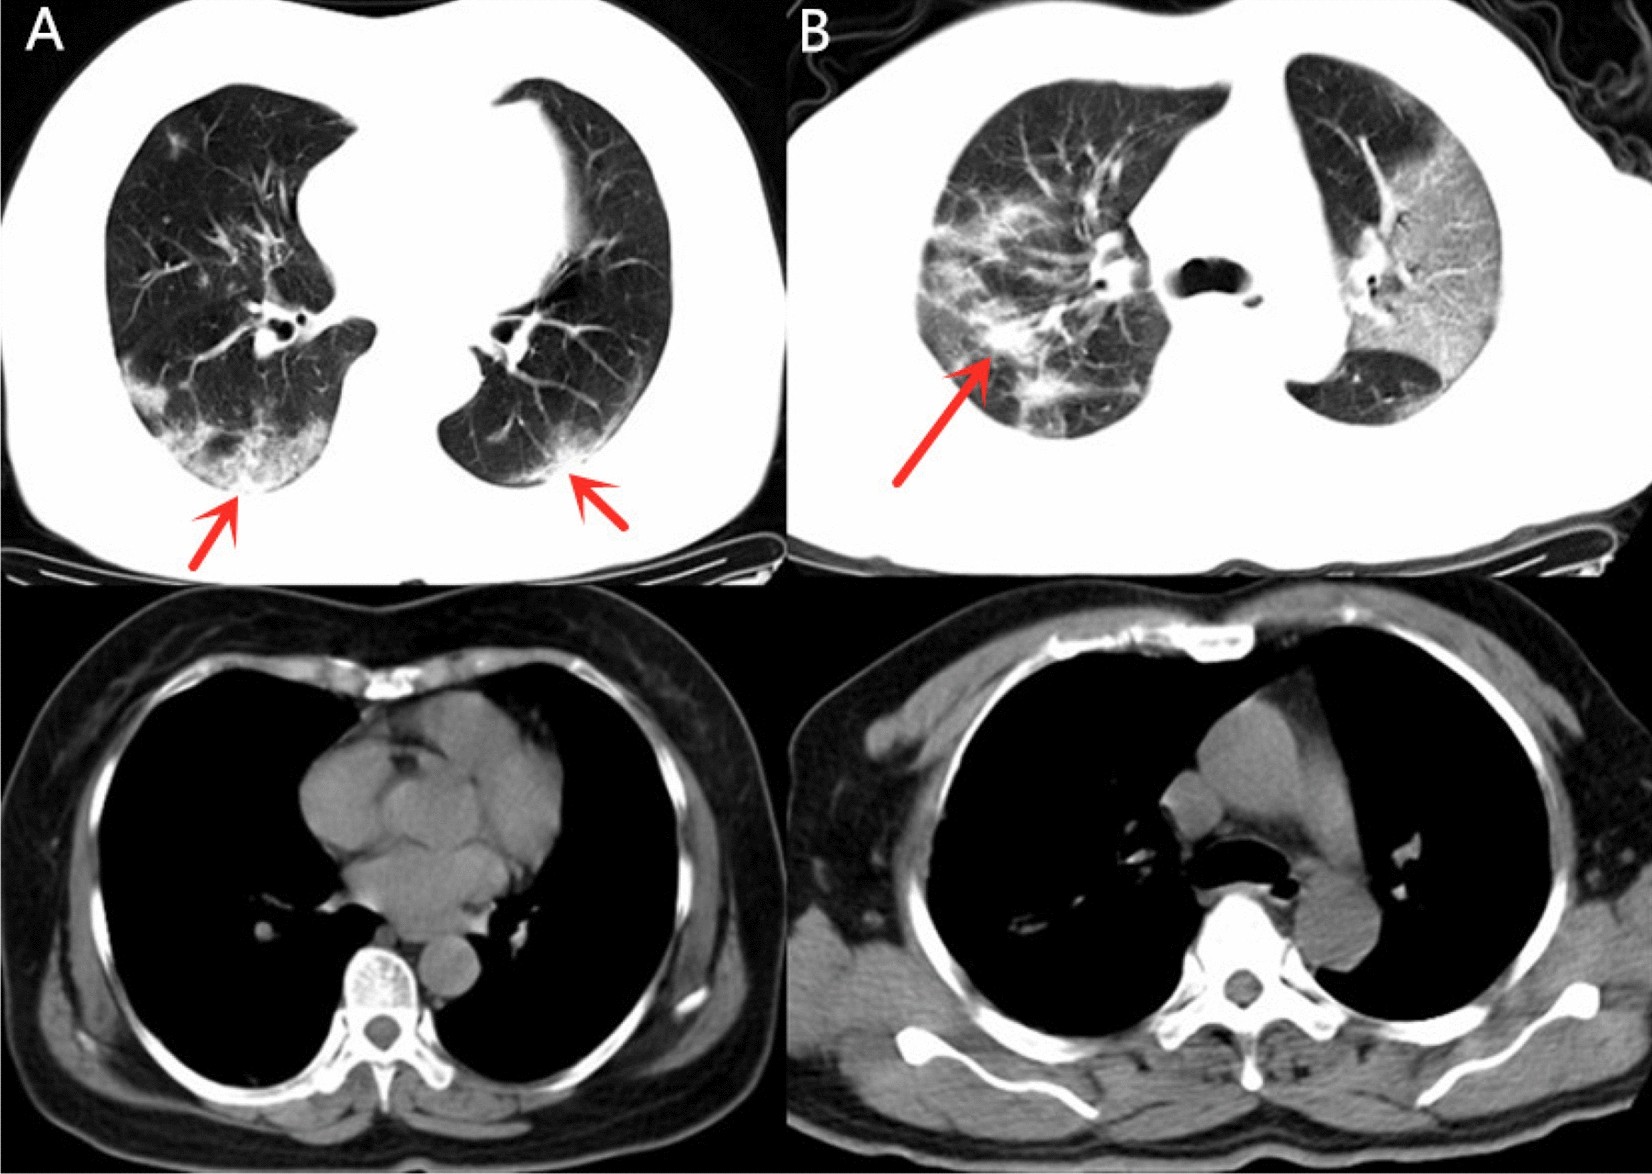

Figure 4

Example of patients with CT demonstrated as GGO > consolidation in Group 1. (A) 65-year-old female with confirmed COVID-19 pneumonia in Group 1 who had hospitalization time of 12 days. CT images demonstrated multiple mixed GGO and consolidation lesions with bilateral distribution, the consolidation component (arrow) was apparently less than GGO. (B) 53-year-old man in Group 1 with 12 admission days. Multiple mixed GGO and consolidation lesions with bilateral distribution were seen in his CT images, at the same time. The range of GGO components was apparently more than consolidation (arrow).